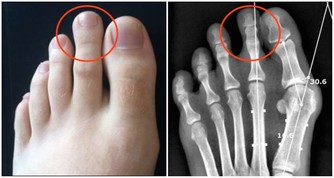

人為什麼會做春夢、被鬼壓床? 這8 種夢或是疾病信號

當然,必須強調的是,這張圖目前主要是根據醫生經驗判斷得出的,疾病導致了某某夢境,僅僅是有可能性,並不一定準確。